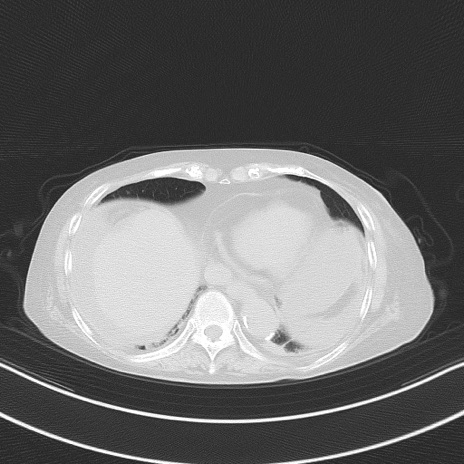

横断像

他院CT